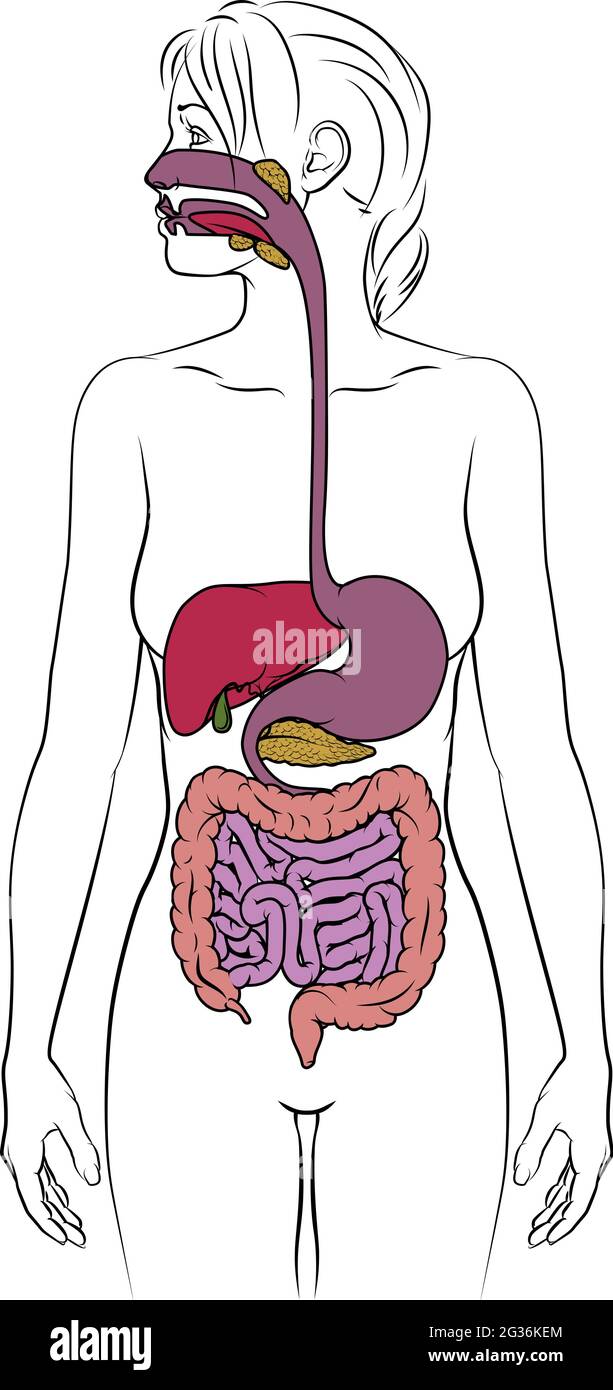

Système digestif humain Femme Schéma anatomique Illustration de Vecteurhttps://www.alamyimages.fr/image-license-details/?v=1https://www.alamyimages.fr/systeme-digestif-humain-femme-schema-anatomique-image334858049.html

Système digestif humain Femme Schéma anatomique Illustration de Vecteurhttps://www.alamyimages.fr/image-license-details/?v=1https://www.alamyimages.fr/systeme-digestif-humain-femme-schema-anatomique-image334858049.htmlRF2ACP2T1–Système digestif humain Femme Schéma anatomique

Système digestif humain Femme Schéma anatomique Illustration de Vecteurhttps://www.alamyimages.fr/image-license-details/?v=1https://www.alamyimages.fr/systeme-digestif-humain-femme-schema-anatomique-image432250188.html

Système digestif humain Femme Schéma anatomique Illustration de Vecteurhttps://www.alamyimages.fr/image-license-details/?v=1https://www.alamyimages.fr/systeme-digestif-humain-femme-schema-anatomique-image432250188.htmlRF2G36KEM–Système digestif humain Femme Schéma anatomique